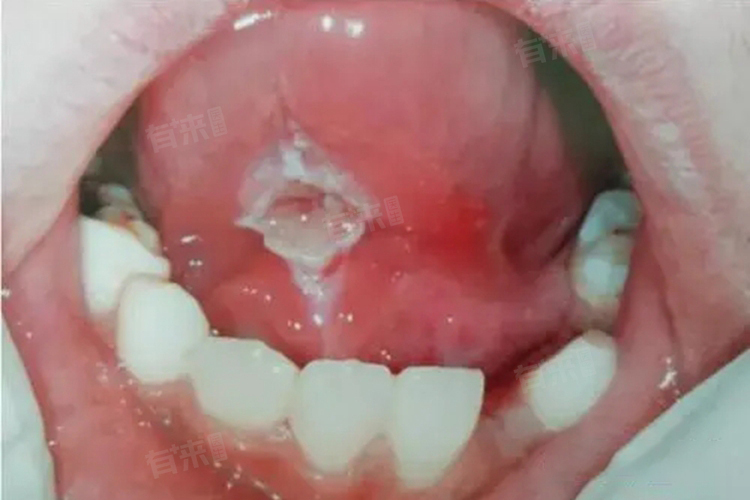

2、口腔溃疡:口腔黏膜局部损伤、免疫力下降等因素,会诱发口腔溃疡。若发生在舌下,初期表现为局部充血,随后形成圆形或椭圆形水泡状病损,伴有明显疼痛。治疗需保持口腔清洁,使用促进愈合的药物,保证充足睡眠,多数可在1-2周内恢复。

3、疱疹病毒感染:感染单纯疱疹病毒后,舌下会出现成簇的小水泡,破裂后形成溃疡,伴有疼痛、灼热感,还可能出现发热、乏力等全身症状。需进行抗病毒治疗,并注意休息,加强营养,提高身体抵抗力,缓解不适症状。